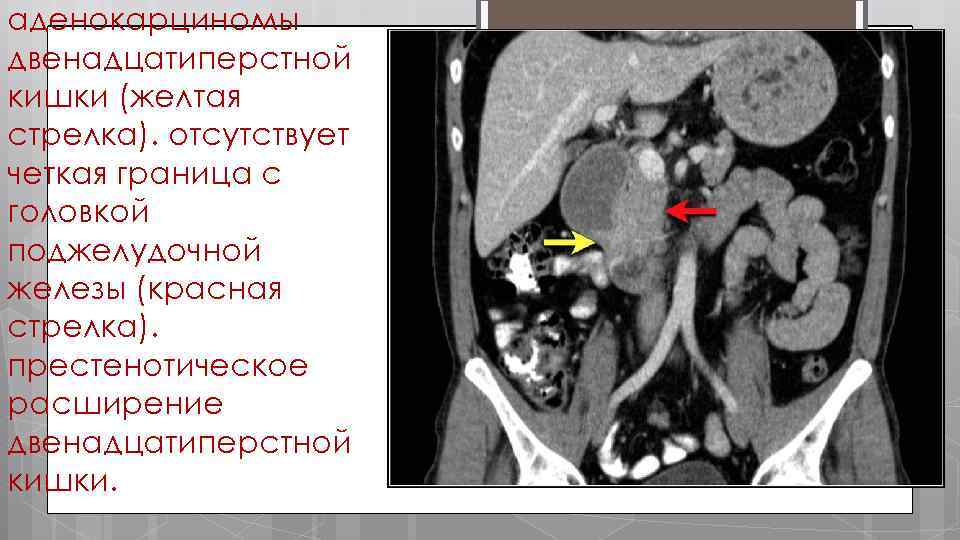

Здесь приведен пример аденокарциномы двенадцатиперстно й кишки с неравномерным утолщением стенок дистальных отделов.

аденокарциномы двенадцатиперстной кишки (желтая стрелка). отсутствует четкая граница с головкой поджелудочной железы (красная стрелка). престенотическое расширение двенадцатиперстной кишки.